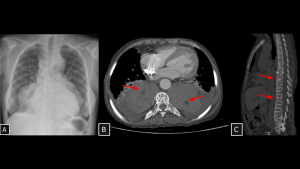

Fig 20: Case 21 – Paravertebral mediastinal metastasis:

A 35-year-old patient with an atypical lipomatous tumor of the right leg (previously operated, with local recurrence demonstrated on MRI (A) developed a heterogeneous solid lesion in the paravertebral mediastinum (arrow in B). The lesion was located anterior and left to the thoracic vertebral bodies and contained foci of fat attenuation (arrows in B and C), consistent with secondary involvement.

SYSTEMATIC APPROACH: 1. Age: Adults / Elderly (History of primary malignancy). | 2. Morphology: Osteolytic bone destruction or conglomerate nodal mass. | 3. Enhancement: Variable (depends on primary). | 4. Relevant Anatomical Relationships: Destroys vertebral body or invades adjacent organs.